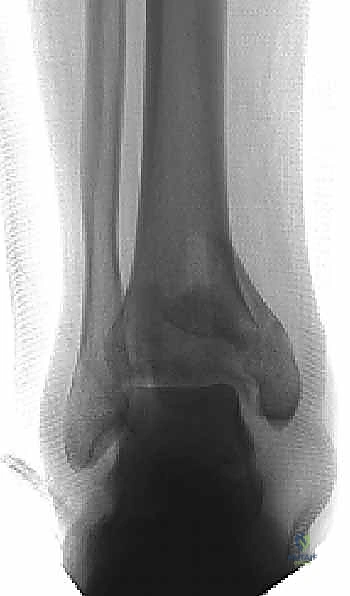

1. التصوير بالأشعة السينية التقليدية (X-Rays)

يتم أخذ صور من ثلاث زوايا (أمامية خلفية AP، جانبية Lateral، ومورتيس Mortise). تعطي هذه الصور فكرة عامة عن نمط الكسر، قصر الساق، ومدى انزياح العظام.

تصنيف كسور البيلون

يعتمد الأطباء على أنظمة تصنيف عالمية لتوحيد لغة التواصل وتحديد خطة العلاج:

* تصنيف رويدي وألجاور (Rüedi and Allgöwer):

* النوع الأول: كسر مفصلي بدون انزياح.

* النوع الثاني: كسر مفصلي مع انزياح، لكن دون تفتت شديد.

* النوع الثالث: كسر مفصلي مع انزياح وتفتت شديد (انفجار المفصل).

* تصنيف AO/OTA: وهو التصنيف الأشمل الذي يقسم الكسور إلى أنواع A (خارج المفصل)، B (مفصلي جزئي)، و C (مفصلي كامل ومعقد).